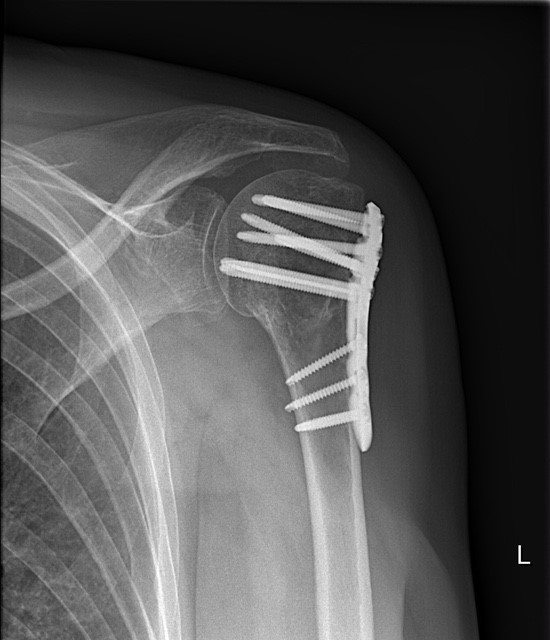

De behandeling van een schouderfractuur hangt af van de aard van de breuk. Voor niet-verplaatste breuken kan een conservatieve (niet-operatieve) behandeling nodig zijn, waaronder rust, een sling en pijnstillers. Bij ernstige of gecompliceerde breuken kan chirurgische interventie nodig zijn om de botfragmenten te herpositioneren en te stabiliseren. Afhankelijk van de soort breuk en type patiënt kan dit variëren van plaat en schroeffixatie, tot fixatie met nagel en schouderprothese.